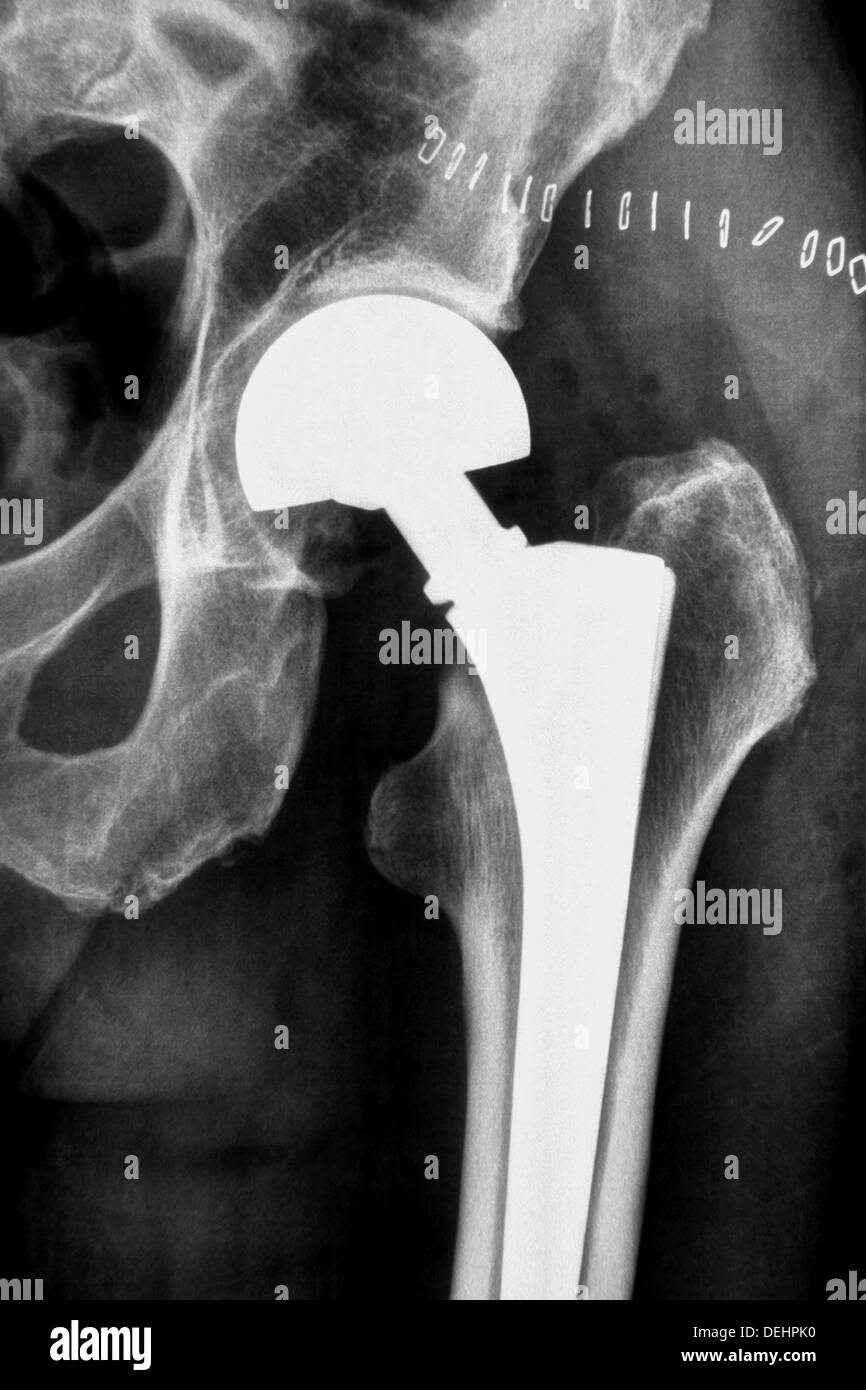

On average, a total titanium hip system replacement weighs between 1 and 2 pounds, according to hipreplacement.com. The weight of the implant will vary according to your size but, in general, may weigh one to two pounds. Both cemented and cementless tha implants proved significantly heavier than the removed bone and soft tissues.

How Much Does A Prosthetic Hip Weigh - How much do hip replacement implants weigh? You will not notice the weight in your. Both cemented and cementless tha implants proved significantly heavier than the removed bone and soft tissues. It would seem that a. The implants we use in most cases are typically made of titanium, with a ceramic head and a polyethylene liner.